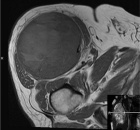

83 year old male with a two month history of a right thigh mass

Zoom image: Radiological image Radiological image.